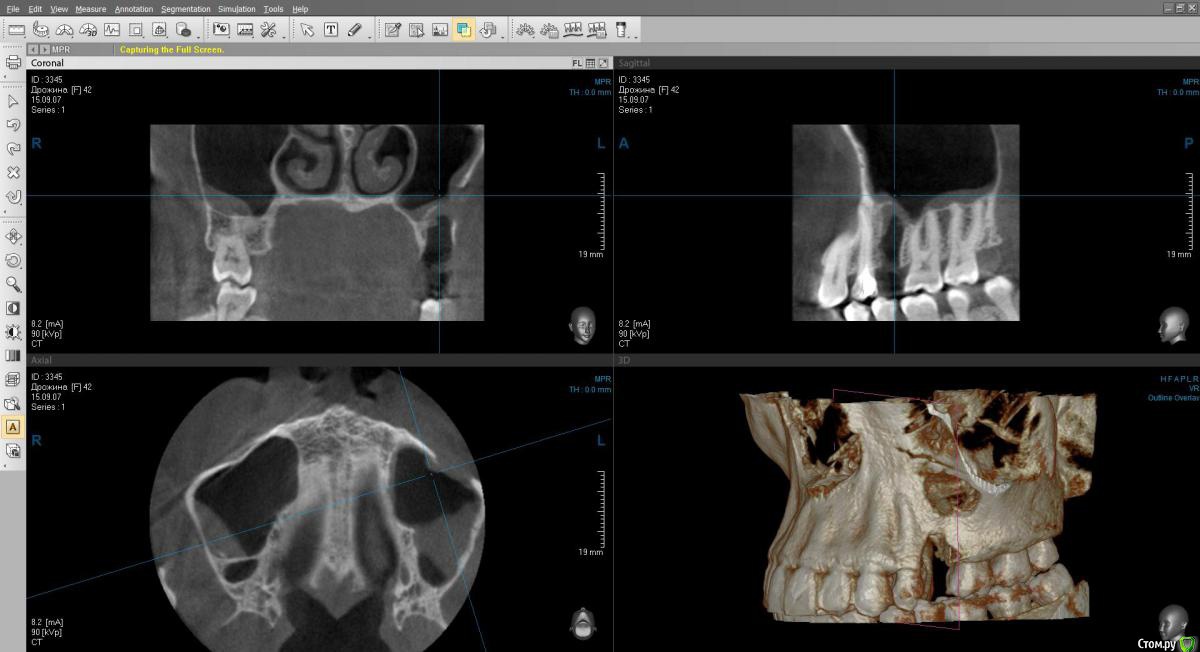

Kostoprav Опубликовано 26 января, 2016 Поделиться Опубликовано 26 января, 2016 если через лунку не получается, в большинстве случаев так оно и есть-трепанирую переднюю стенку пазухи и убираю корень, желательно после сделать рентген контроль Ссылка на комментарий